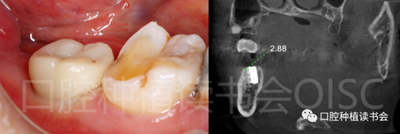

5.4.3 術(shù)后第10周,47戴入最終種植冠,X片確認(rèn)基臺就位準(zhǔn)確(圖25),以30N.cm扭矩旋緊基臺螺絲(圖26)。

5.4.4 種植冠封閉螺絲孔后,調(diào)合,拋光,完成最終修復(fù)(圖27);戴牙前CBCT顯示:種植體頰側(cè)骨板厚度為2.88mm;47種植冠獲得了良好的穿齦輪廓,并維持了正常的頰側(cè)牙弓輪廓。

通過術(shù)前CBCT的仔細(xì)分析,確認(rèn)該患者符合后牙即刻種植的適應(yīng)證。拔牙前利用殘根進(jìn)行精確定位,實(shí)施微創(chuàng)的不翻瓣手術(shù),結(jié)合使用親水表面種植體及骨膠原植骨材料,并采用了合理的創(chuàng)口封閉方案?;颊咴诎窝篮蟮?0周就完成了最終修復(fù)及種植體負(fù)重,顯著縮短了整體治療時(shí)間,并大大減輕了種植治療中的疼痛不適。